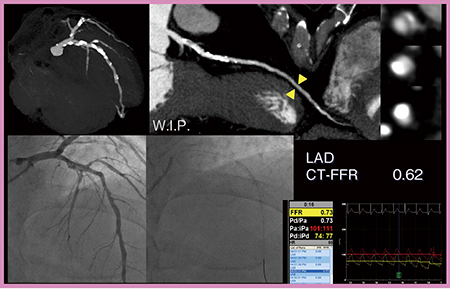

症例4は,労作時の息切れを主訴に狭心症(三枝病変疑い)精査目的で当院を受診した。カテーテルFFRにてLADとLCXを測定した結果,LADは0.73と低下しており,CT-FFRでも0.62と低下していた(図5)。LCXもCTAにて狭窄が疑われたが,カテーテルFFRは0.93,CT-FFRも0.91と正常であった(図6)。本症例は,CT-FFRの診断能でカテーテルFFRの省略が可能な症例と言える。

図5 症例4:狭心症(三枝病変)疑い症例のLADのカテーテルFFRとCT-FFR(W.I.P.)